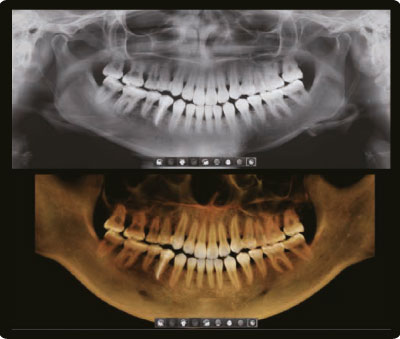

Одно сканирование = Два изображения

Одно сканирование с Green Smart Vatech позволяет получить не только КТ, но и панорамное изображение. Это означает, что пациенты, которым нужны оба исследования не будут подвергаться дополнительному облучению. Кроме того, оба этих исследования можно просматривать в одной программе.